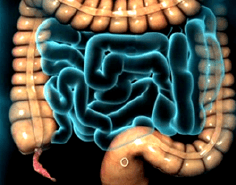

Colon

Los pacientes pueden presentar múltiples patologías en el Colon que requieren de manejo quirúrgico:

Enfermedad Diverticular y Diverticulitis

Los divertículos son dilataciones de la mucosa colónica, los cuales pueden ser múltiples y presentar como complicación sangrado o inflamación y perforación. Esta enfermedad puede operarse de forma programada, cuando estos divertículos no presentan complicación en agudo; sin embargo, en algún momento ya han generado cuadros previos de inflamación y se realiza una resección del segmento afecto con inmediata conexión de los segmentos sanos. También pueden requerir de manejo quírurgico de urgencia en el caso de presentar inflamación severa o perforación, en donde en base a los hallazgos se ofrece la mejor opción quirúrgica a los pacientes.

Cáncer

El cáncer de colon tiene actualmente una alta frecuencia y en estados avanzados tiene un pronóstico desfavorable, es por ello, que se requiere de un diagnóstico y tratamiento oportuno con la finalidad de obtener los mejores resultados quirúrgicos y la mayor sobrevida para el paciente. Es por ello que se ofrece un manejo integral mediante un diagnóstico temprano por Colonoscopía y manejo quirúrgico seguro, adecuado y oportuno para el paciente.

Estomas

Los pacientes pueden ser portadores de estomas por múltiples causas (trauma abdominal, procesos inflamatorios agudos, perforación intestinal o colónica, cáncer). Sin embargo, en la mayoría de los casos se puede retirar el estoma y volver a conectar el intestino o colon, restableciendo el tránsito intestinal normal, para lo cual llevamos una serie de estudios preoperatorios de Imagen y Endoscopía, con la finalidad de ofrecer la mayor seguridad y asegurar los mejores resultados para el paciente.

Este tipo de cirugías se pueden llevar a cabo mediante Laparoscopía o realizarse cirugía abierta, por lo que se tiene que valorar cada caso en particular, con el fin de ofrecer los mejores beneficios, los menores riesgos y la mayor seguridad para el paciente.